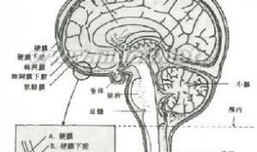

脑膜刺激征检查视频,直观解析临床诊断技巧

你有没有想过,去医院看病的时候,医生有时候会给你来点“特殊待遇”?比如说,给你做个脑膜刺激征检查。这听起来是不是有点陌生?别急,...